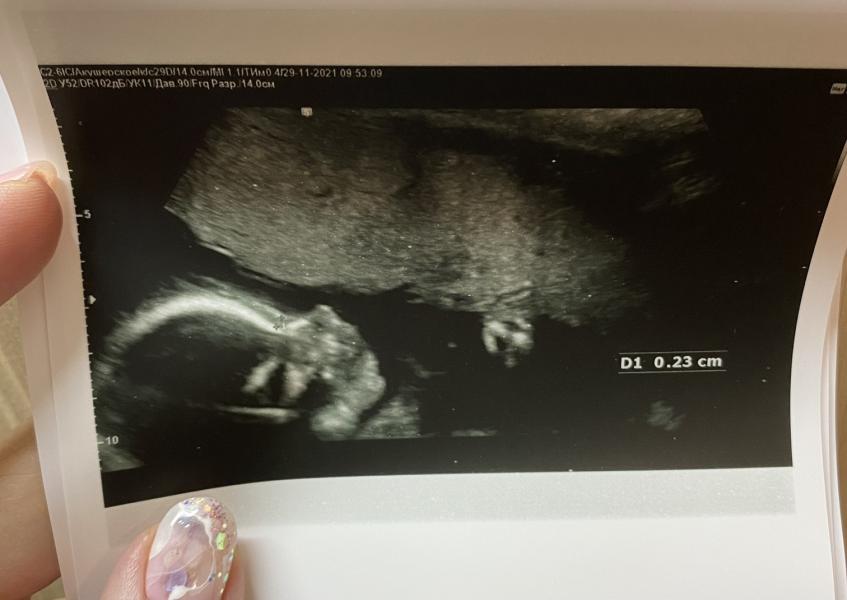

На память ❤️